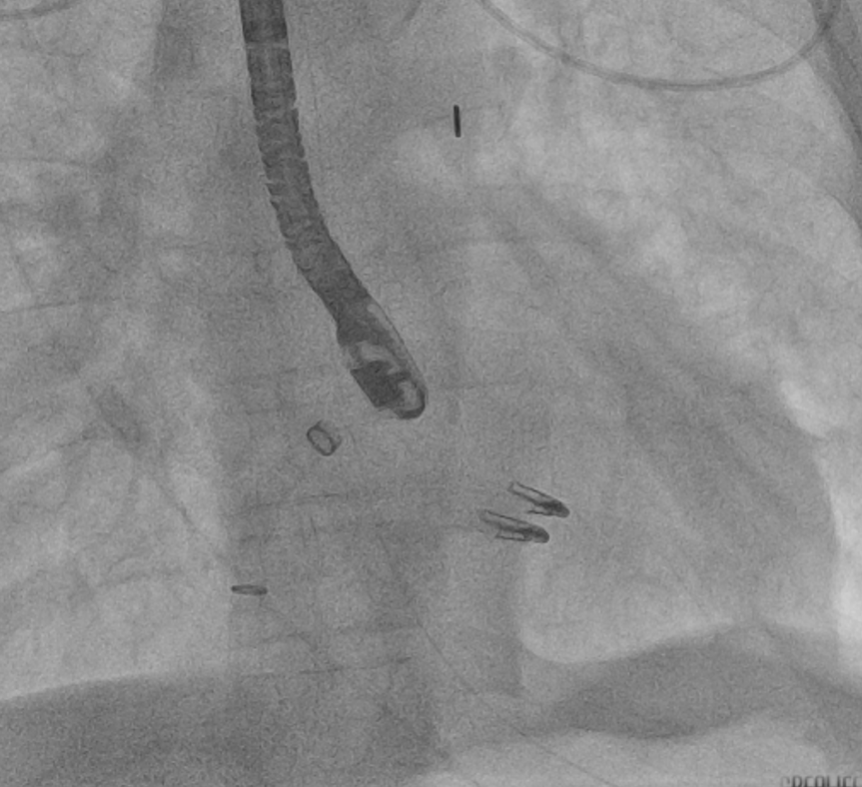

患者症状未有缓解迹象,仍然胸闷喘憋明显,血压和血氧饱和度进一步下降,周亚峰副院长、赵良平主任迅速评估,决定行急诊经皮二尖瓣钳夹术。该技术在心肌梗死后早期需要紧急干预的高危患者中,已经证明了其可行性和良好的疗效,然而风险极高。医生团队经与家属充分沟通取得信任,立即于全麻下行经皮二尖瓣钳夹术,术中经食道超声见该患者二尖瓣前叶整个A2 A3区完全脱垂,乳头肌收缩期甩入左房侧,二尖瓣极重度反流。术中为患者植入2枚二尖瓣夹(MitraClip),尽可能减轻了二尖瓣反流程度。术中即刻食道超声提示二尖瓣反流下降,肺静脉逆流消失,左房压LAP由术前43/15(24)mmHg降至23/14(17)mmHg。术后转入ICU进一步治疗,复查心脏彩超提示二尖瓣返流较前明显改善,继续主动脉内气囊反搏(IABP)1:1反搏改善后负荷、呼吸机辅助通气。

植入2枚二尖瓣夹